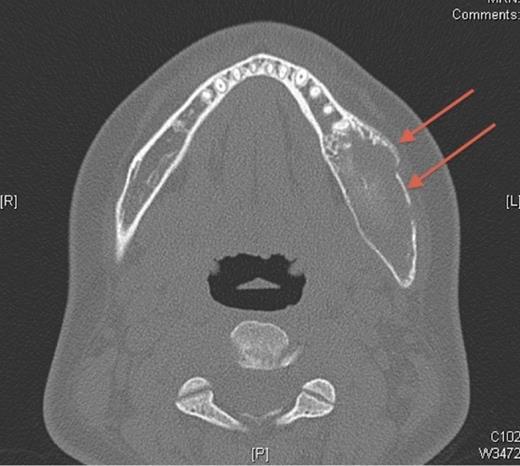

In October 2007, the patient represented with a swelling around the left angle of the mandible. Radiographs revealed no abnormalities but oral antibiotics were commenced with the clinical impression being that of osteomyelitis. Over the following month the swelling fluctuated in size, therefore a CT scan was undertaken. This showed a cystic enlargement at the left angle of the mandible with no cortical disruption or soft tissue involvement. With symptoms persisting the patient underwent exploration of the area under general anaesthesia and histopathology (which had previously been negative) now revealed desmoplastic fibroma.

Pre-operative axial CT showing the lesion in the left side of the mandible (denoted by arrows).

A desmoplastic fibroma often behaves in an aggressive manner and macroscopically has a firm consistency with well-defined advancing surfaces that may extend into surrounding soft tissue. It is usually seen radiographically as a well-demarcated, radiolucent lesion. However, CT and MRI offer the best imaging of the lesion(5). The initial facial asymmetry in this case was most likely caused by the desmoplastic fibroma that was not evident on plain radiographic imaging. Further to this the lesion was not clinically active in the 4 years pre-operatively or evident at osteotomy. It was only in the post-operative period that the lesion was diagnosed, albeit following an initial negative histology